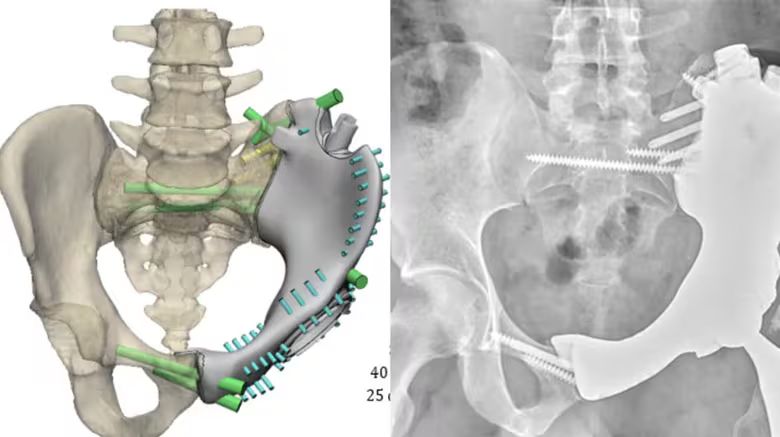

A 29-year-old U.S. Army staff sergeant was referred after being diagnosed with chondrosarcoma in the left side of his pelvis.

10 years ago, the only options after resecting the cancer would be to amputate the leg or leave a flail leg. In this case, our sarcoma team opted to replace the removed bone with a custom 3D-printed implant.

More about the case: cle.clinic/42Zr8pR